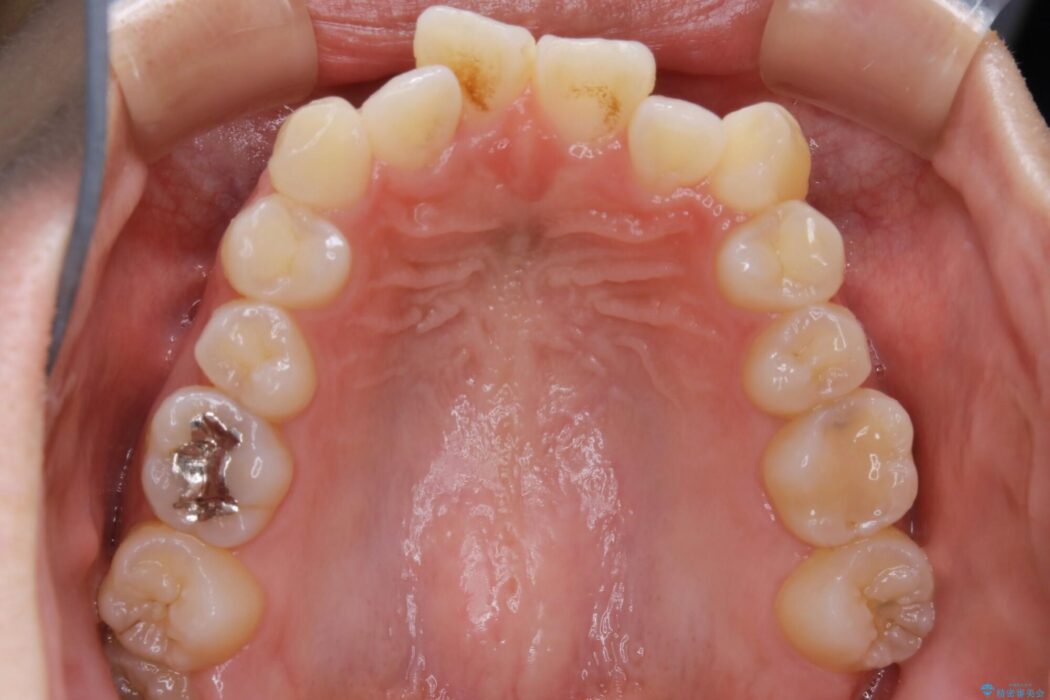

特に前歯部分に90度近く捻転した歯、斜めに生えている歯などによる歯列のがたつき、正中のズレが目立っていました。

奥歯から遠心移動とディスティング(歯の側面を僅かに削る)を行うことで歯列を整えるスペースを確保し、患者様のご要望からインビザライン装置での矯正を計画しました。

本症例では奥歯から順に移動させるため前歯の変化を感じるには時間が掛かりましたが、インビザライン装置とマイクロインプラントを併用することで健康な歯を抜歯することなく歯列をきれいに整えることができました。